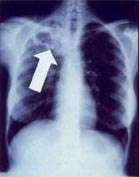

Chest X-ray and CT

In active pulmonary TB, infiltrates or consolidations and/or cavities are often seen in the upper lungs with or without mediastinal or hilar lymphadenopathy or pleural effusions ( tuberculous pleurisy). However, lesions may appear anywhere in the lungs. In disseminated TB a pattern of many tiny nodules throughout the lung fields is common - the so-called miliary TB. In HIV and other immunosuppressed persons, any abnormality may indicate TB or the chest X-ray may even appear entirely normal.

Abnormalities on chest radiographs may be suggestive of, but are not necessarily diagnostic of, TB. However, chest radiographs may be used to rule out the possibility of pulmonary TB in a person who has a positive reaction to the tuberculin skin test and no symptoms of the disease.

Cavitation or consolidation of the apexes of the upper lobes of the lung or the tree-in-bud sign[7] may be visible on an affected patient's chest X-ray.[1] The tree-in-bud sign may appear on the chest CTs of some patients affected by tuberculosis, but it is not specific to tuberculosis.[7]